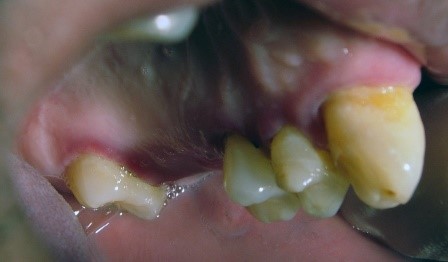

Appendix: Photo- and Radiographs of Periodontal Disease Associated With HIV

Photographs courtesy of Dr. Gwen Cohen Brown and the Dental Hygiene Department of New York City College of Technology

Figure 1: Patient with linear gingival erythema (LGE)

Figure 2: Patient with necrotizing ulcerative periodontitis (NUP)

Figure 3: Patient with linear gingival erythema (LGE) and necrotizing ulcerative periodontitis (NUP)

Figure 4: Patient with necrotizing ulcerative gingivitis (NUG)

Figure 5: Patient with localized bone loss